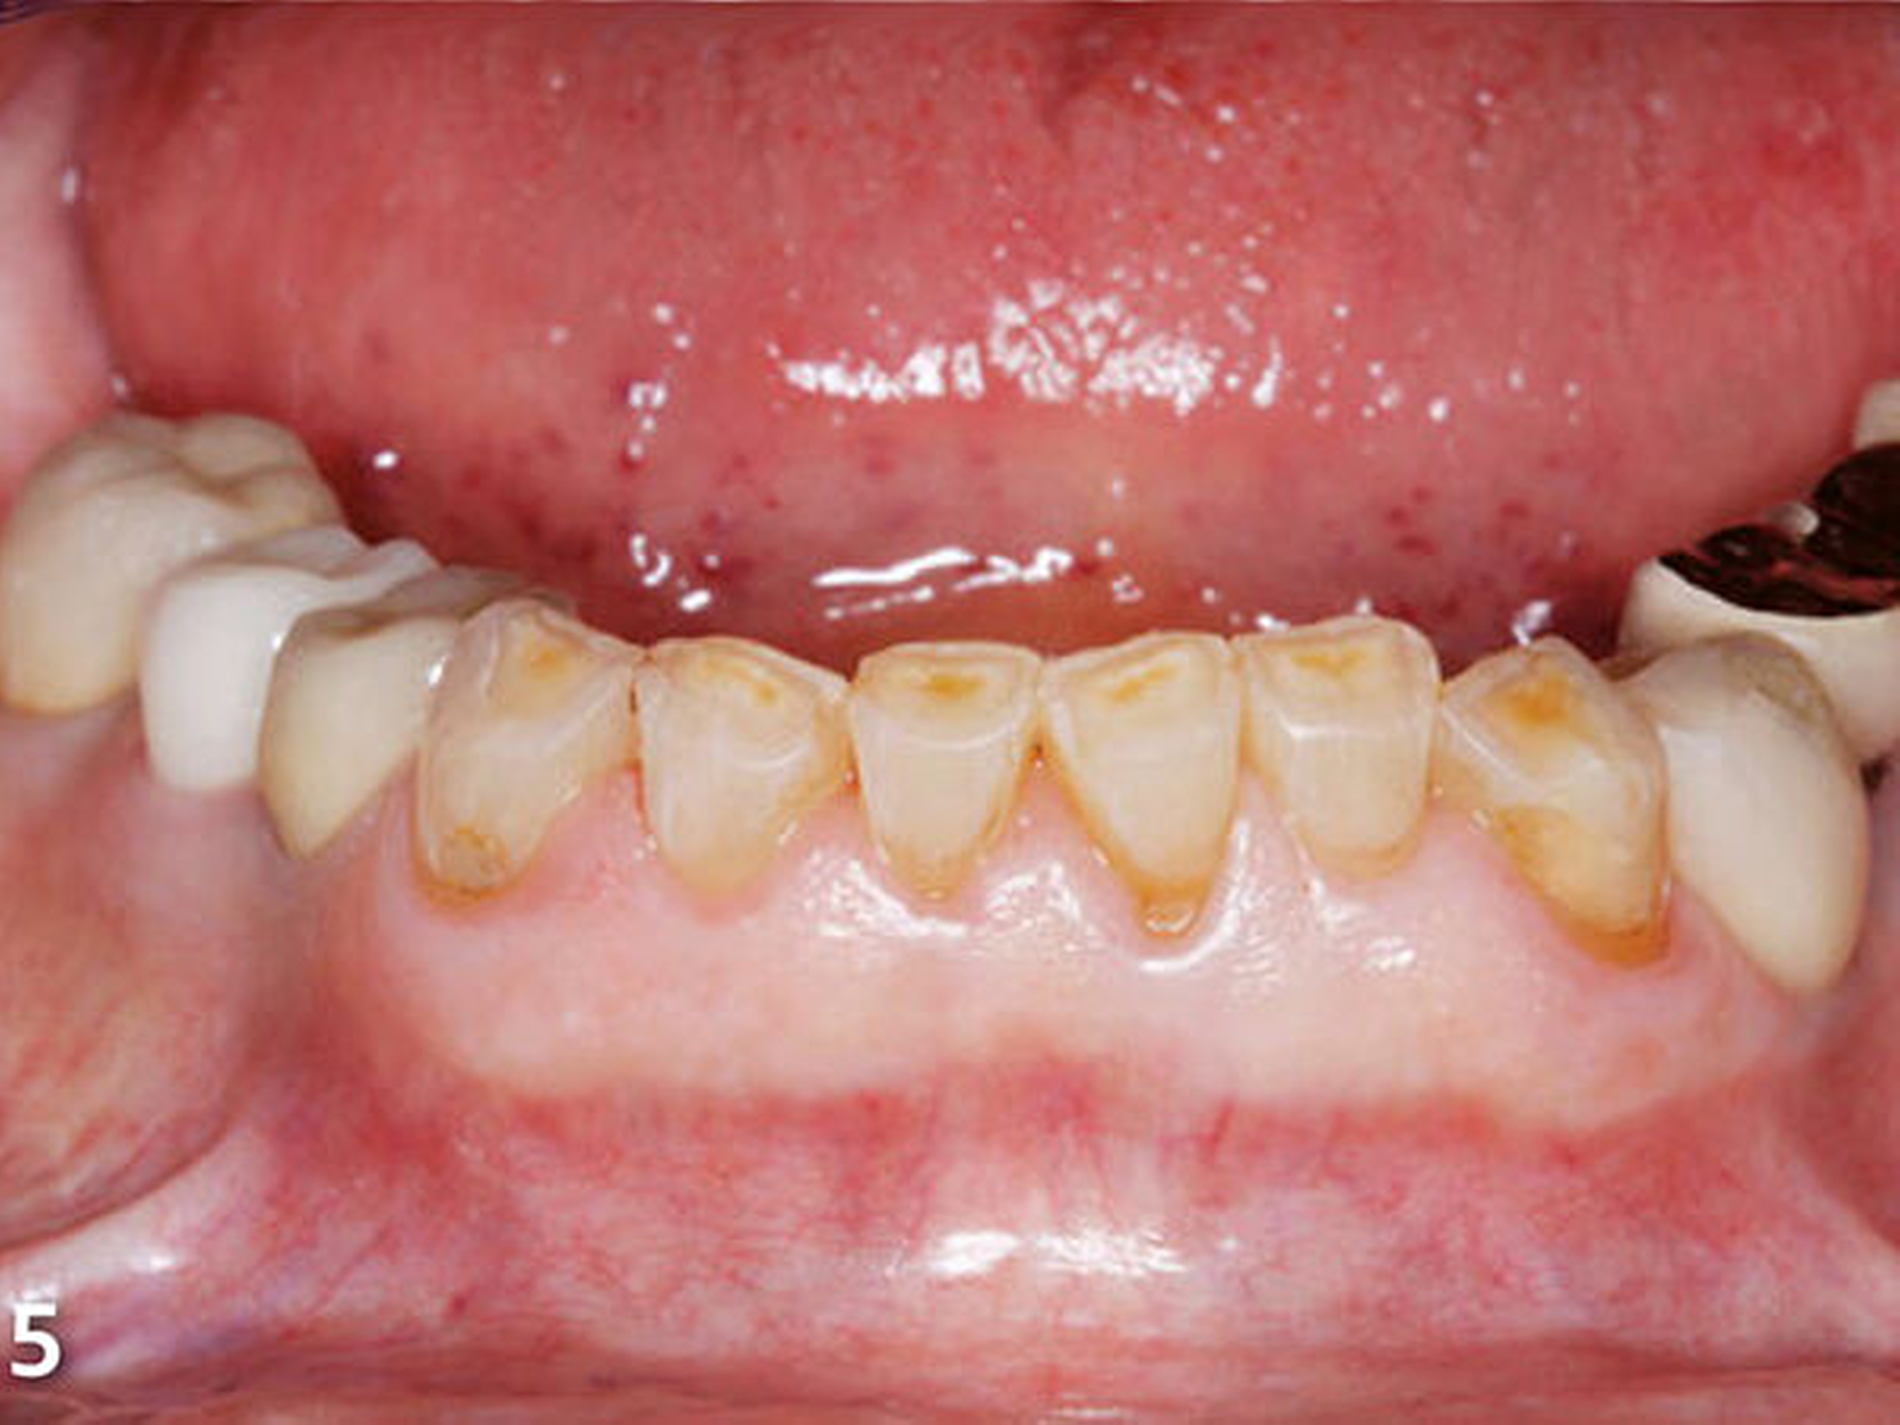

Insbesondere störten die Patientin aber der gravierende Farbunterschied der Unterkieferfront zu den Keramikverblendungen der Rekonstruktionen des Oberkiefers und die Form bzw. Größe der unteren Frontzähne (Abb.5). Darüber hinaus entsprachen die insuffizient ausgeformten Kauflächen der Restaurationen der Unterkieferseitenzähne nicht den Anforderungen an eine funktionsorientierte Gestaltung der okklusalen Anatomie (Abb.6).